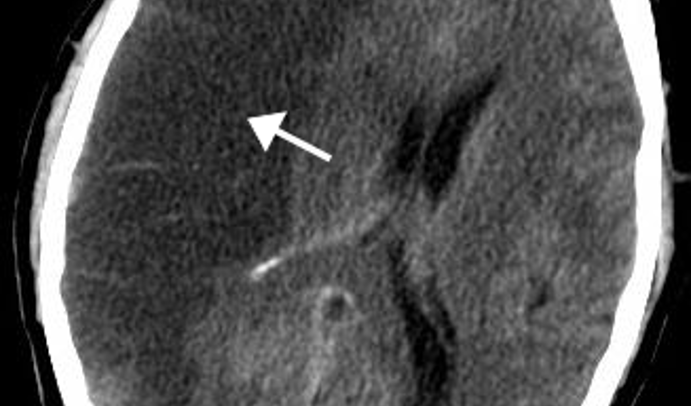

Which stroke has the following appearance on a head CT?

dark; may be normal w/in first 24 hours

ischemic stroke